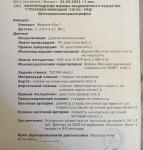

Здравствуйте. Ситуация такая. Ходили насуши в 14 мая, сказали ООО закрылось, но увеличена скорость кровотока, но это возрастное и пройдёт. Сегодня педиатр сказала что увеличение скорости это порок, и никак иначе. Я пошла переделала узи платно, так опять увидели, но только не ООО а ДМПП типа 3 мм (но ведь раньше его не было) . Но пишут как- то странно, я и не поняла, могли ли с ООО ПЕРЕПУТАТЬ, ведь размеры одни и теже что были "до". Результаты узи прилагаю. Не знаю что делать, куда бежать. Ребёнку 2 мес. Что могло стать причиной? Во времена Б не болела ничем. Откуда это могло взяться. Помогите пожалуйста разобраться.

Добрый день! Третий день не сплю, прошла много инфо о ДМПП и ООО. И вот у меня появился ещё такой вопрос: в протоколе узи указано -" дефект перегородки в области овального окна". Может ли быть что это не ДМПП а само незакрытое ООО? Ранее ещё 16 апреля в другой больнице нам ставили ООО -3,2 мм, но немо каком ДМПП печи не шло. Далее, 14 мая на узи уже у другого врач, было сказано что ООО закрылось, но есть небольшое увеличение кровотоку и это возрастное (и я ещё у врача переспросила про пороки, она скащпдамрисего нет, все у вас хорошо) , а теперь вообще ставят порок. Что делать и как быть. Направления никуда не дали, на учёт не поставили. Сказали понаблюдаем. Были у неврологов, она говорит что не похожи мы на сердечника - вес набирается хорошо, ребёнок активный, не капризный. Развивается соответственно возрасту. Кожные покровы не Бледные и носогубный треугольник не синеет. Наткнулась на многие истории где Деичм ставили ДМПП, а в итоге оказывалось ООО. Может ли быть и у нас такая же ошибка, скажите пожалуйста, есть ли такая вероятность. И с размерами в 3мм, нужна ли операция или оно все- таки затянется само. Ребёнку сейчас 2,5 мес. Заранее спасибо за ответ.

До этого, сыну делали Узи (14.05.21) , 1 мес и 2 недели было ему. И ничего не видели. Кому верить не знаю? Куда идти тоже. Кардиологов нет у нас. В кардиоцентр педиатр направление не даёт. протокол узи от 14.05.21 (фото к нему не делали) прикрепляю. Помогите пожалуйста